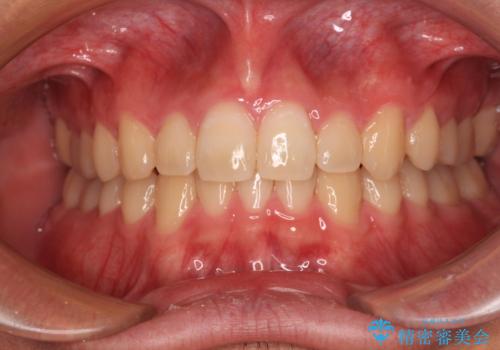

欠損した前歯とディープバイト ワイヤー矯正で短期間で治療

傾斜しいている大臼歯を立ち上げながら、下顎歯列を上顎に対して前方位となるように工夫し、デコボコを解消した上でディープバイトも改善することができました。